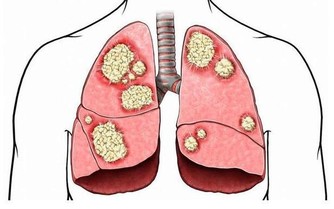

維生素C也稱為抗壞血酸,是人體必需營養素,還可緩解白癜風、預防癌症等。